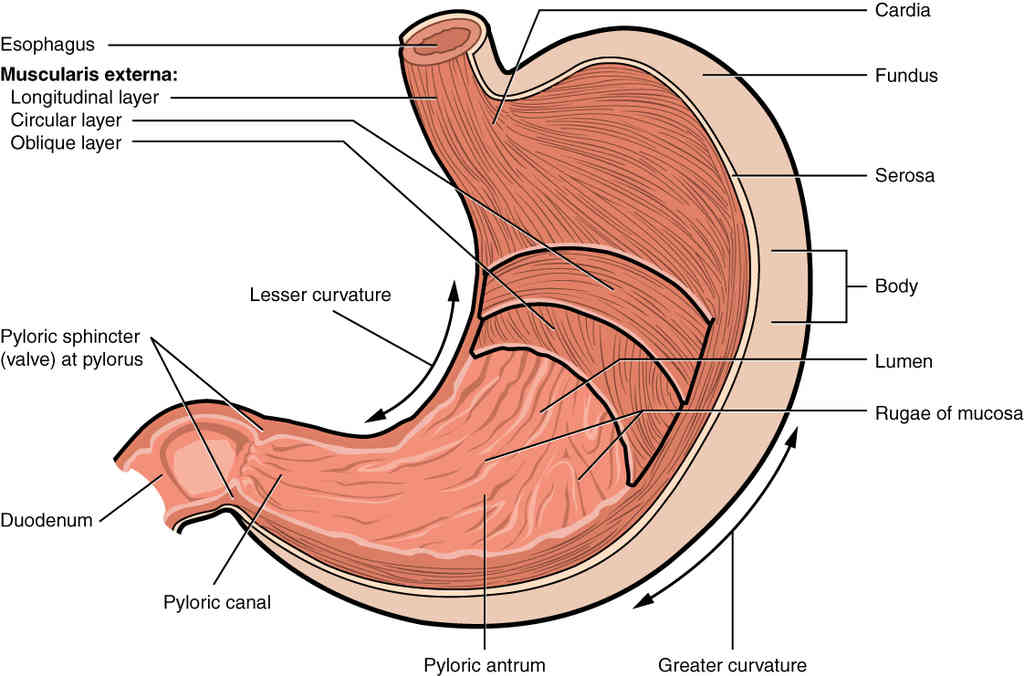

This page is under construction. For now, it is just a resource of the images found in the OpenStax Anatomy and Physiology Handbook. It wil slowly change into a revision tool. Each slide has a number. Use this to refer to the slide. When completed, it will have an unlabelled section, with labelled slides in parallel. On the unlabelled slides, write your answer and use the labelled slide to assess yourself. Keep track by also noting the number on each slide. Improvement at each attempt is important, more so than full marks on a first attempt.